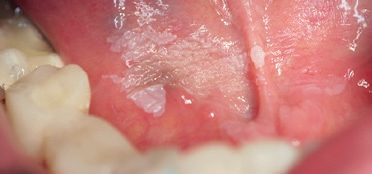

Leukoplakien sind weißliche Veränderungen der Schleimhaut. Sie gehören zu den häufigsten intraoralen Präkanzerosen [8]. Jede 100. Frau und jeder 50. Mann in Deutschland hat eine Leukoplakie [8]. Die Leukoplakie ist eine nicht abwischbare, weißliche Veränderung, der keine andere Erkrankung zugrunde liegt [9]. Bei der Leukoplakie handelt es sich zunächst um eine klinische Diagnose ohne eindeutigen histopathologischen Befund [10]. Neben der Farbe ist die Beschaffenheit der Leukoplakie wichtig. Klinisch wird zwischen homogenen und inhomogenen Leukoplakien unterschieden. Die homogene Leukoplakie (Leukoplakia simplex) zeigt sich als einheitliche, weißliche Fläche, die gelegentlich von Rissen durchbrochen wird (Abb. 1) [5,11]. Sie ist dünn, eventuell transluzent und liegt mit einer relativ scharfen Begrenzung der Schleimhaut auf [12–14]. Sie wird auch als Präleukoplakie bezeichnet und als mögliche Vorform der eigentlichen Leukoplakie diskutiert [11].

Ohne eine histopathologische Untersuchung ist eine Differenzierung häufig nicht möglich. Dies zeigt der in Abbildung 3 dargestellte klinische Fall. Diese Schleimhautveränderung stellte sich klinisch als eine homogene Leukoplakie dar und entpuppte sich nach histologischer Untersuchung als ein Plattenepithelkarzinom der Mundhöhle im frühen Stadium (Carcinoma in situ).